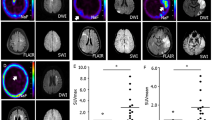

Injections of 18F-FDG were performed with the tip of the microcatheter located in the CCA (n = 3), in the iICA (n = 3) or in the tail vein (n = 3). Catheter tip placement in the CCA resulted in a markedly more intense uptake of 18F-FDG in the ipsilateral extra- and intracranial tissues compared to contralateral tissues (Figs. 1d and 2b, e). With this catheter position, the uptake was most prominent in the extracranial compartment (Fig. 1d); the anatomical distribution of the tracer was identical to the opacification following injections of iodine contrast in the CCA, showing that intra-arterial injection in this location resulted in distribution predominantly in the extracranial space (Fig. 1c, d). However, even with this catheter position, the uptake in the hemisphere ipsilateral to the injection tended to be higher than the uptake in the contralateral hemisphere, although without reaching significant difference at equilibrium (Fig. 2b, e). On the other hand, placement of the catheter tip in the iICA resulted in an intense uptake in the left cerebral hemisphere only, corresponding to 9.2 times higher uptake compared to the CCA injection at equilibrium after 25 min (p = 0.009) (Figs. 1b and 2a, d, g). Also, when comparing the ipsilateral cerebral hemisphere to the contralateral hemisphere after iICA injection, the difference was 9.2 times higher (p = 0.008) (Fig. 2a, d, g). The areas with high uptake corresponded to the cortical areas supplied by the iICA (Fig. 2a, d). The cerebral uptake of 18F-FDG after iv injection was 8.69 times lower than after the iICA injection (p = 0.004) (Fig. 2a, c, d, f, g). Extra-cranial 18F-FDG uptake was lower after iICA and CCA injections than after the iv injection (Fig. 2a–f). Systemic uptake levels were higher after the CCA injection than after the iICA injection, consistent with a higher extraction of 18F-FDG in the brain compared to soft tissue (Fig. 2a, b, d, e).

Distribution of 18F-FDG and iodine contrast media following selective intra-arterial injections in the internal and common carotid arteries. a Digital subtraction angiography (DSA) and b 18F-FDG PET, following injection in the left internal carotid artery (iICA), showing perfusion and uptake in the left hemisphere. c DSA and d 18F-FDG PET, following injection in the left common carotid artery, showing perfusion of extra- and intracranial vasculature and 18F-FDG distributions, respectively. PET images are volume-rendering technique 3D projections and are summed over 25 min

Distribution and changes in tissue radioactivity of 18F-FDG following selective intra-arterial injections in the internal and common carotid arteries and systemic injections in the tail vein. 18F-FDG PET, transaxial and coronal planes, following: a, d injection in the left internal carotid artery (iICA); b, e injection in the common carotid (CCA); c, f injection in the tail vein. g Changes in tissue radioactivity over time expressed as percentage of the injected dose per gram tissue (%ID/g; Y axis = log10 mean %ID/g) following: injection in the iICA in the left (ICA LH, red dot) and the right (ICA RH, purple square) cerebral hemispheres; following injection in the left CCA in the left (CCA LH, green triangle) and the right (CCA RH, yellow inverted triangle) cerebral hemispheres; following i.v. injection (IV, blue rhombus). The differences in mean values at 25 min are significant between ICA LH and ICA RH (p = 0.009), ICA LH and CCA LH (p = 0.008) and between ICA LH and IV (p = 0.004). PET images are summed over 25 min. Error bars indicate ±1 SD